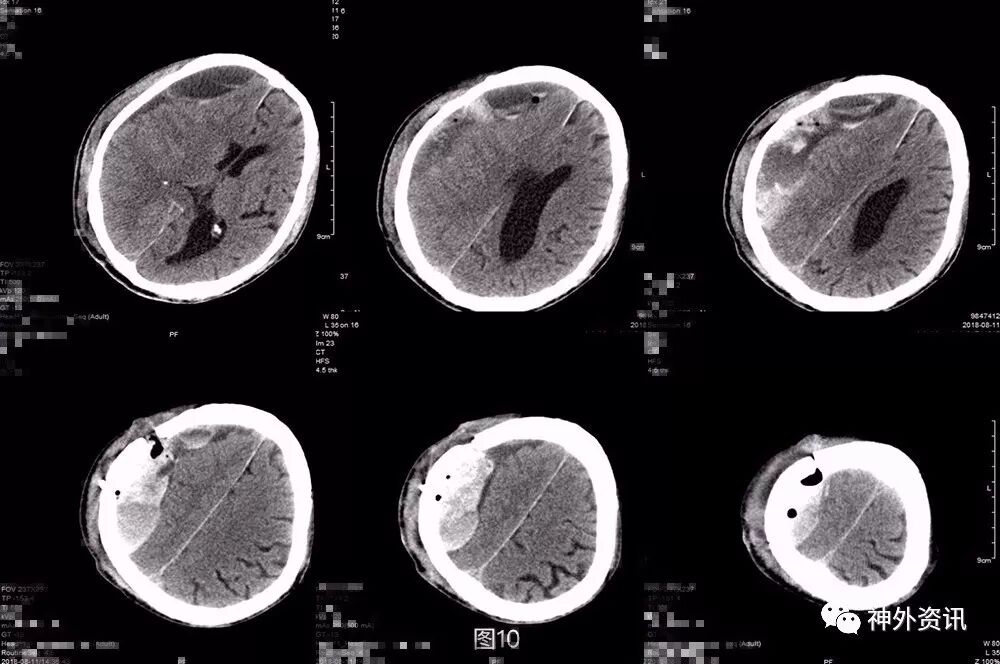

第三次术后第5天再次复查头颅CT,显示局部积气比前片吸收,但积血积液仍较明显(图9)。考虑患者神志及肢体肌力基本同前,继续予以药物保守治疗。之后患者逐渐神志转清,左侧肢体肌力好转至3-4级,期间复查头颅CT(图10)提示局部积血密度逐渐下降,提示血肿液化可能,于术后半月稳定后转康复治疗,定期复查头颅CT。

图10. 第三次术后第10天,局部积血密度逐渐下降,提示血肿液化可能。